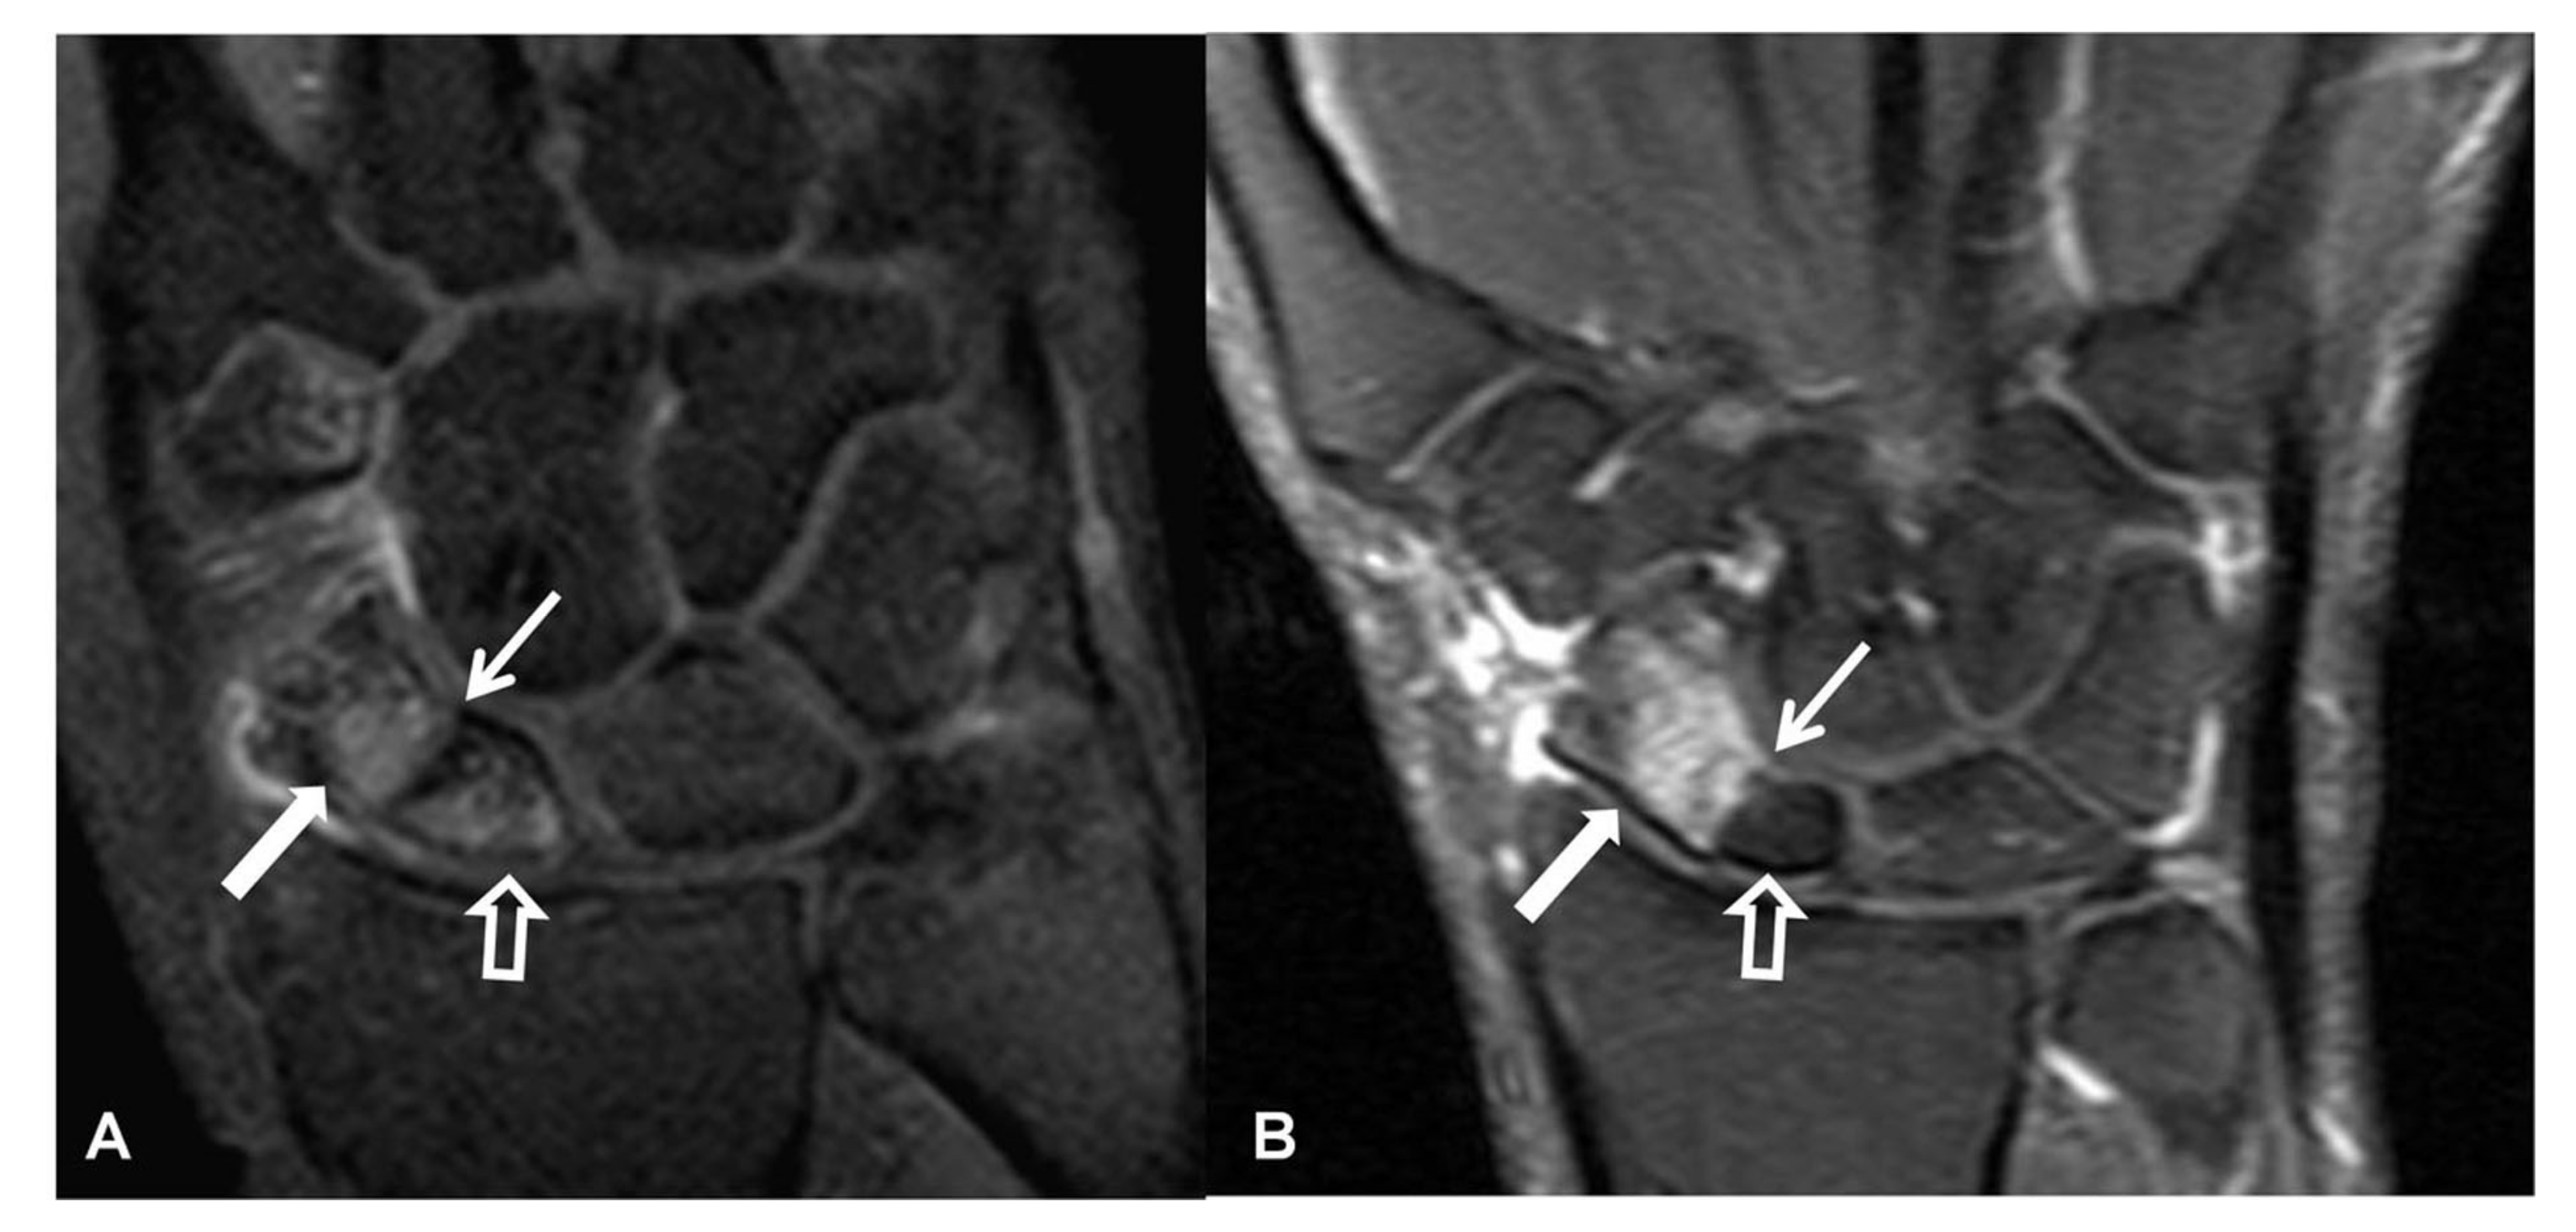

Magnetic resonance imaging (MRI) and MRI-arthrography (MRa) should be included in the diagnosis of SLAC and SNAC as they provide superb imaging of the osseous and soft tissue structures. In addition, MRI is a robust approach for the evaluation of carpal OA as it can directly evaluate the bone marrow and the osteoarticular deformities (Figure 10). Moreover, MRI can evaluate the vascularity of the bone marrow by estimating the degree of enhancement (Figure 11).

Figure 10.

A 56-year-old male patient with SLAC and SNAC wrist. Coronal T1w (left) and T2* (right) MR images, showing the proximal pole scaphoid necrosis (arrow), the scapholunate diastasis with proximal capitate bone migration (open arrow), the rotation of the lunate bone (arrowhead) and the subchondral cysts secondary to osteoarthritis development (short arrows).